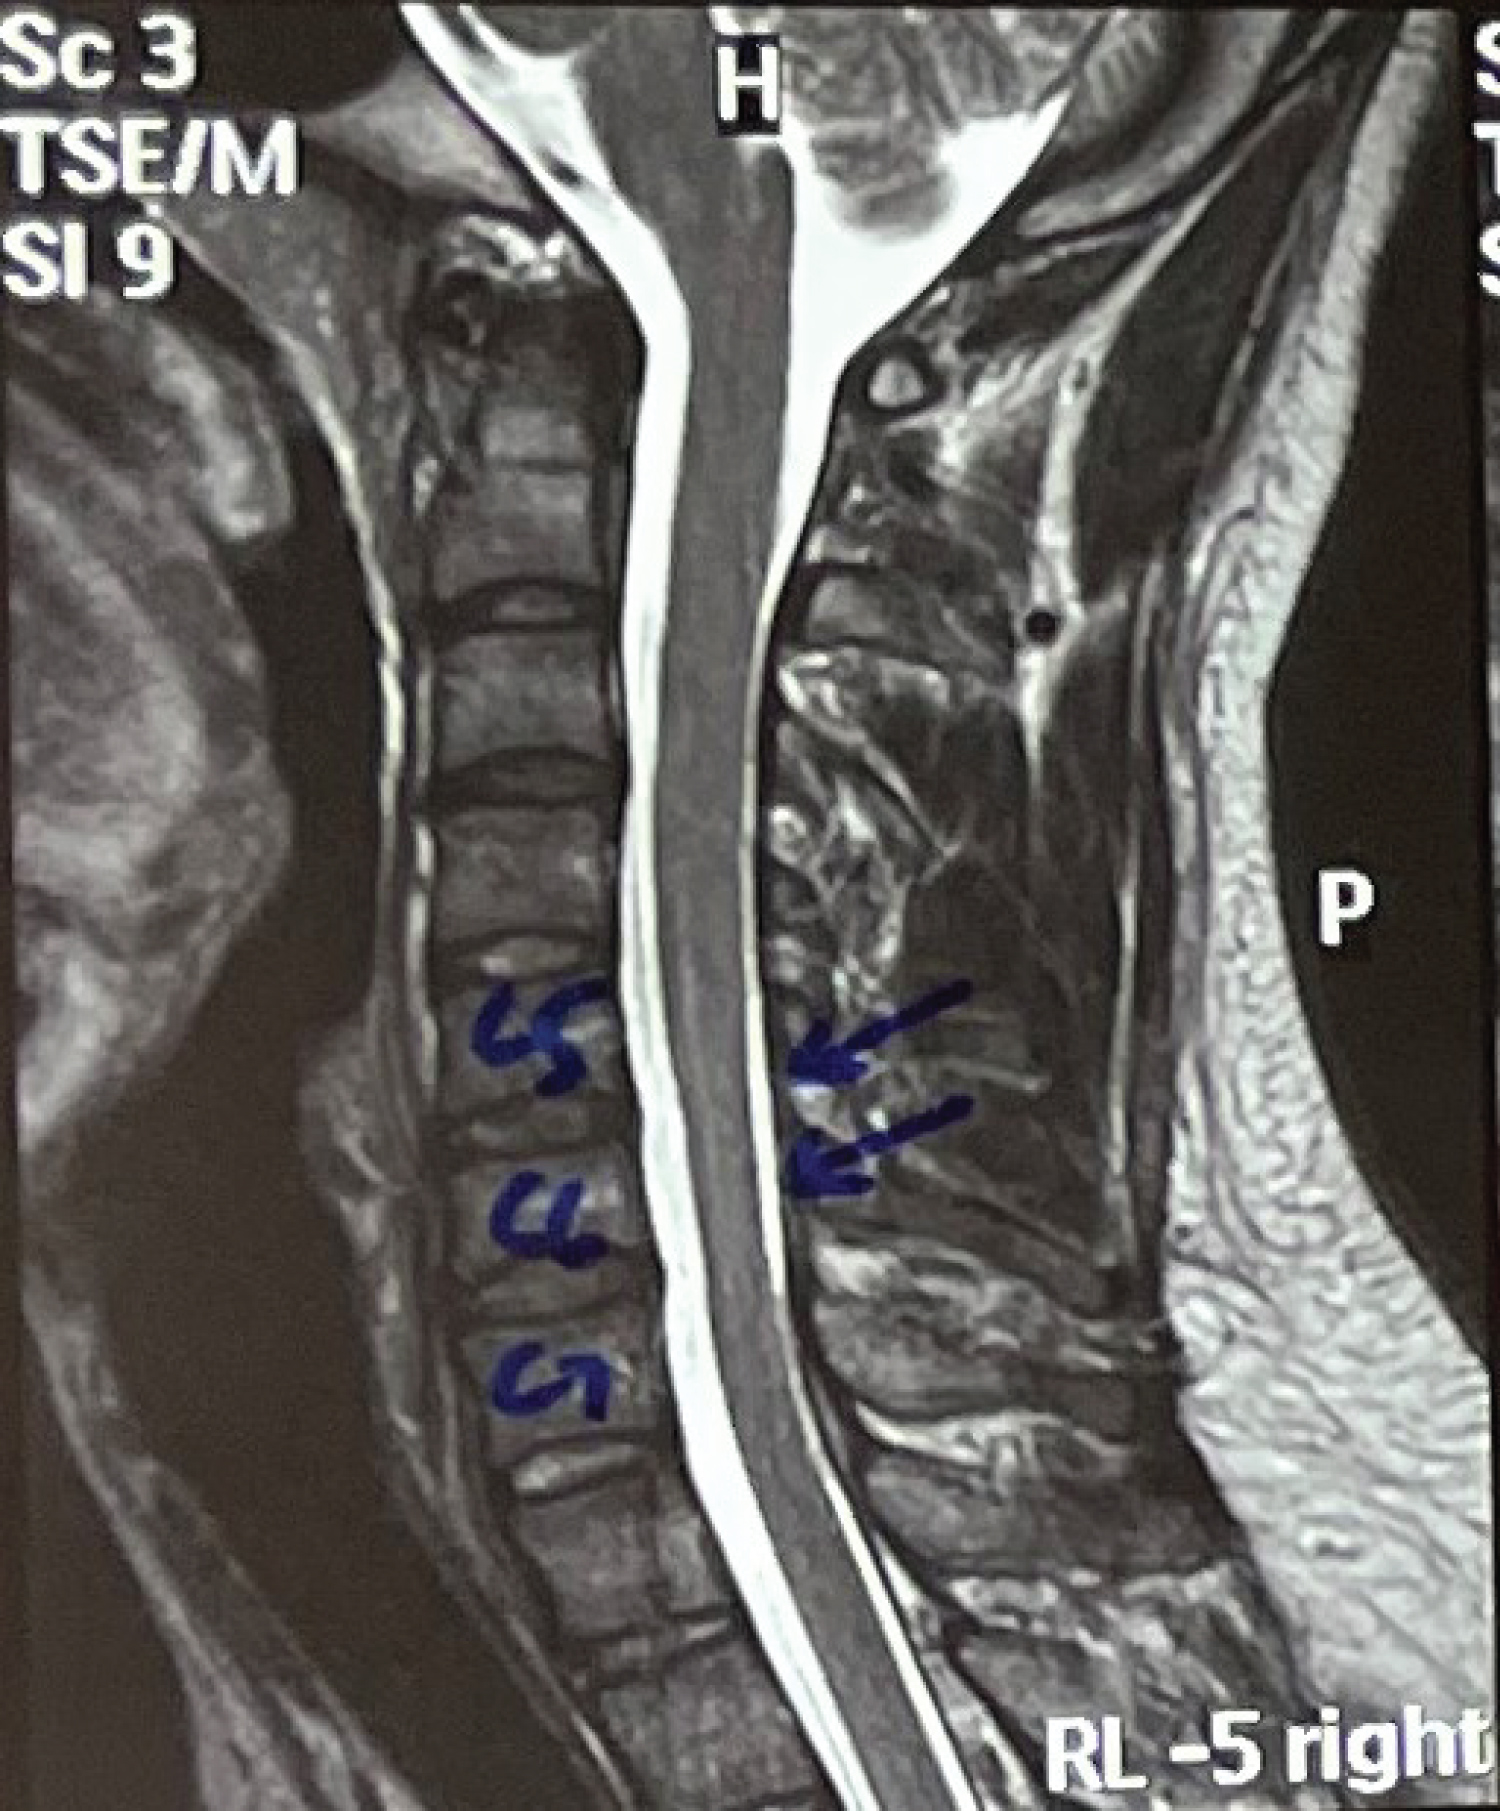

A twenty-one-year-old male right-handed came to us with a chief complaint of weakness in the grip of both hands (right > left) which was noticed by him in August 2020 when he was gathering clay with his bare hands to make a Ganesha idol. He experienced that this weakness was static and non-progressive and was not related to any aggravating or relieving factors. The patient also had a history of occasional tingling in both of his hands since childhood which was left unattended. The patient started noticing the loss of the bulk of his bilateral hand muscles. The patient did not have weakness in proximal upper limbs or any of the lower limbs. He did not have any complaints regarding bowel and bladder habits. On examination, we found wasting of thenar as well as hypothenar muscles (Figure 1 and Figure 2). The patient had asymmetric weakness in all his intrinsic muscles (3/5) of both hands. All the sensations were well preserved and deep tendon reflexes were normal. The nerve conduction studies, and EMG findings were suggestive of bilateral C8-T1>>C7>>C5-C6 very chronic motor axon degeneration with the site of involvement likely to be at anterior horn cell or cord level. His MRI of the cervical spine (Figure 3, Figure 4 and Figure 5) was showing focal atrophy of the lower cervical spinal cord from C5-C6 to C6-C7 disc levels with mild prominence of the central canal and on flexion, there was the ventral movement of posterior dura with the prominence of the posterior epidural venous plexi extending from C3 to upper dorsal levels. All these findings were suggestive of Hirayama disease. The patient was advised to wear a cervical collar and on follow up after two months he had relief from his tingling and there was an improvement in power (4/5) of intrinsic muscles of both hands. He was able to write in reasonably good handwriting and was able to perform all his routine activities without any disturbances.

Figure 4: Sagittal T2 image after neck flexion showing the ventral movement of the posterior dura with the prominence of the posterior epidural venous plexi extending from C3 to upper dorsal levels (Shown with blue arrows). View Figure 4